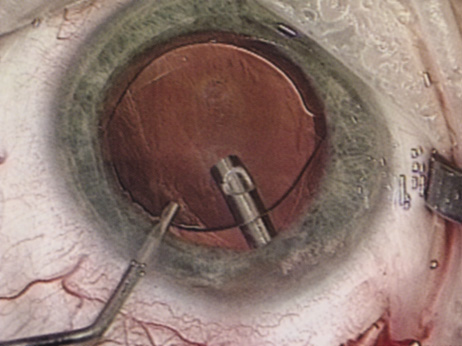

Although slit-lamp examination can give the ophthalmologist an excellent estimate of endothelial health, sometimes a formal assessment of the corneal endothelial cell density is helpful (Fig. 4). This information is most likely to be helpful in advising patients who may be at greater risk of postoperative corneal decompensation. Specifically, patients with cornea guttata, previous ocular surgery, history of blunt ocular injury,56 exfoliation syndrome,57 iridocorneal-endothelial syndromes,58 or a history of glaucoma59 are known to have reduced endothelial cell counts. Patients with a history of acute angle closure are at particular risk because each episode of elevated intraocular pressure can damage endothelial cells.60

There are qualitative and quantitative methods for endothelial cell evaluation. Cell density can be measured directly with an endothelial cell camera. The surgeon also should view the photograph and qualitatively estimate the regularity of the endothelial cell mosaic. Some instruments calculate a coefficient of variability and percent of hexagonal cells.

When an endothelial cell camera is not available, qualitative assessment of count and cell morphology can be accomplished at the slit-lamp using a technique called specular reflection.61 The ophthalmologist focuses a narrow parallelepiped on the corneal epithelium, directing the beam at the periapical cornea from a 45-degree angle. The slit beam is moved slowly from side to side until the bright corneal reflex strikes the examiner's view from the epithelial surface reflection (first Purkinje-Sanson image). On high magnification, the examiner should focus on the endothelial surface just next to the bright reflex. The image of the endothelial mosaic will come into view. The surgeon can make a qualitative assessment of the cell density and degree of regularity. With practice, these estimates can be surprisingly accurate.

The implications of a reduced endothelial cell count are primarily prognostic and can provide the surgeon with more information to help counsel the patient about the risk of corneal decompensation with cataract surgery. Gentle phacoemulsification without triple procedure is recommended when cornea is clear and compact, given that a significant number of patients may be able to avoid a corneal transplant despite uncountable cell densities. However, these patients should be advised that they may be at an increased risk of requiring a corneal transplant.